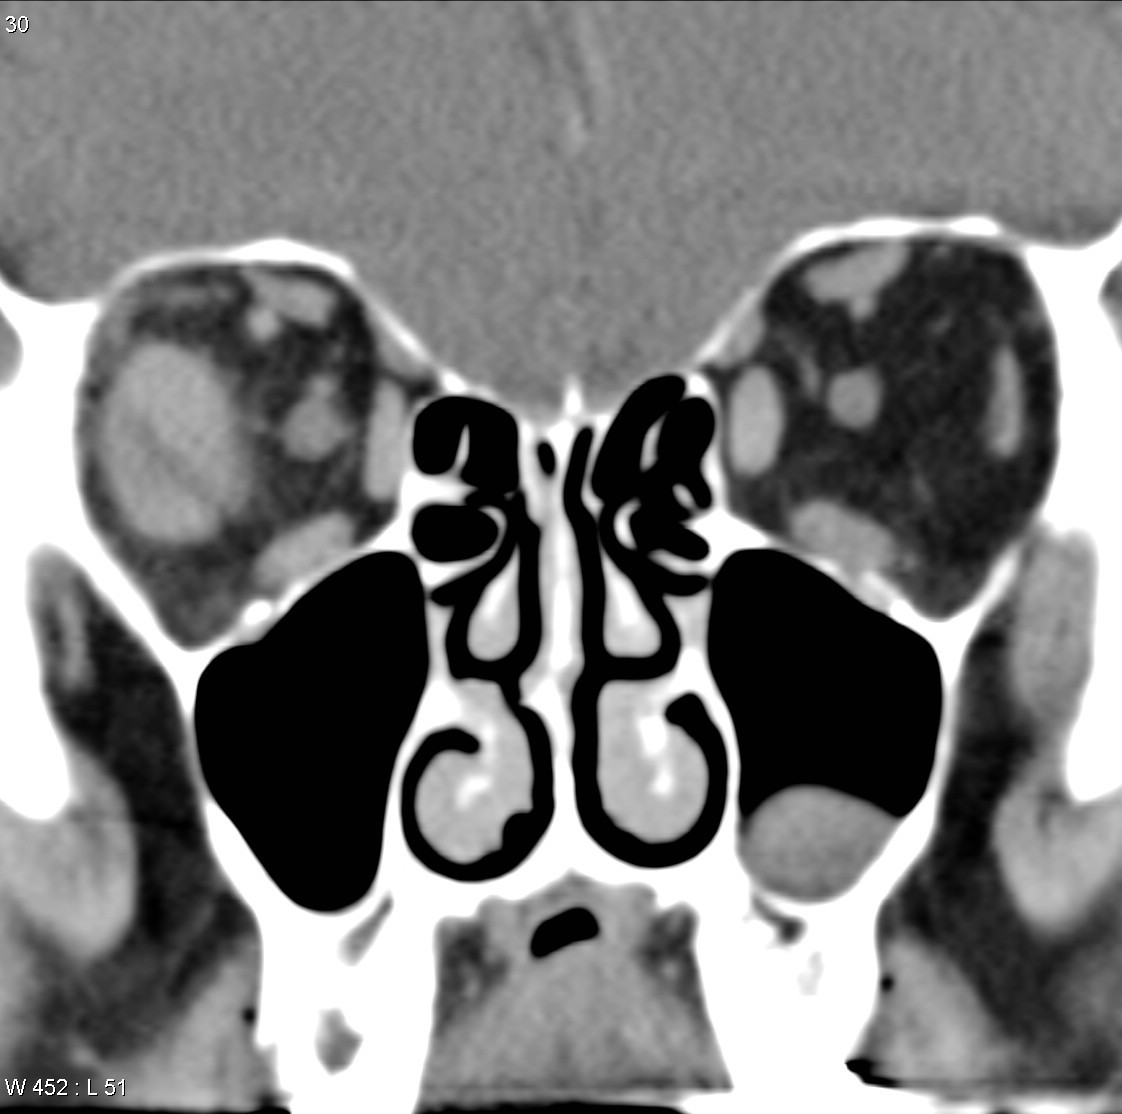

https://www.researchgate.net/figure/Bilateral-Sturge-Weber-syndrome-Postcontrast-axial-MR-image-A-shows-gross_fig1_14472655

Bilateral Sturge-Weber syndrome. Postcontrast axial MR image ( A ) shows gross leptomeningeal thickening and enhancement related to the right hemisphere and less extensive abnormality of the left occipital region. Unenhanced axial T1-weighted image ( B ) shows thickening of the posterior globes bilaterally; after administration of contrast material ( C ), marked enhancement is seen in both globes. Abnormal high signal is present in this region on the proton density–weighted image ( D ). Bilateral, diffuse choroidal hemangiomas were found at ophthalmoscopy (not shown).